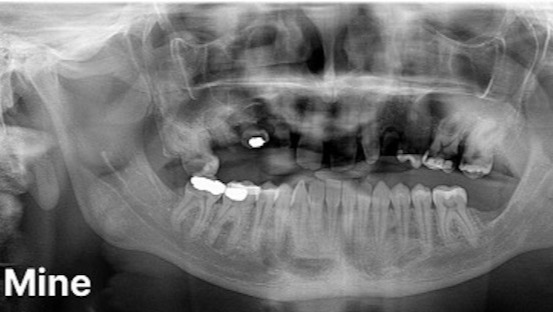

Le jeune homme de 26 ans est atteint d’une forme d’hypodontie génétique. Il lui manque ainsi cinq dents d’adultes et toute ses dents de sagesse. Ses cinq dents de lait qui auraient dû tomber naturellement sont restées en place trop longtemps, aucune dent ne se trouvant dessous pour les faire tomber. Elle ont ainsi commencé à pourrir à l’intérieur de sa bouche.

Ses autres dents se détériorent égaement rapidement. Tristen, qui perd des bouts de dents chaque mois, raconte que frotter sa langue contre ses dents est «comme la frotter sur du verre brisé». Il ne lui reste plus que cinq ou six dents du haut intactes.

Une dentition normale comparée à celle de Tristen